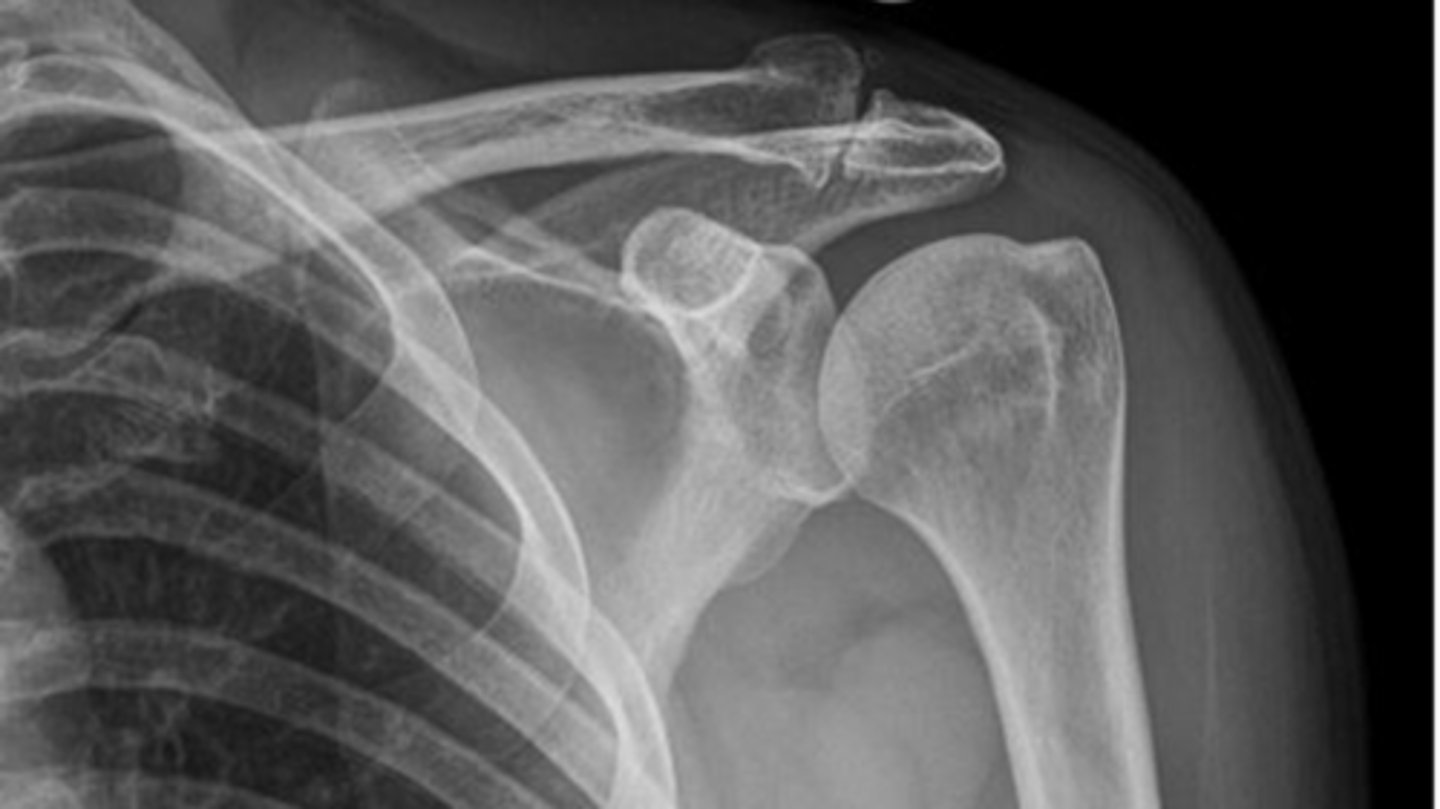

ACJ OA -- A (alignment) = osteophyte formation on either side of the acromion, C (cartilage space) = loss of AC joint space

What is this image depicting? How do you know?

ACJ OA

What is this image depicting?

1. A (alignment) = osteophytes

2. B (bone density) = sclerosis

3. C (cartilage space) = loss of space

Which 3 MAIN things are you looking for when it comes to classifying OA?